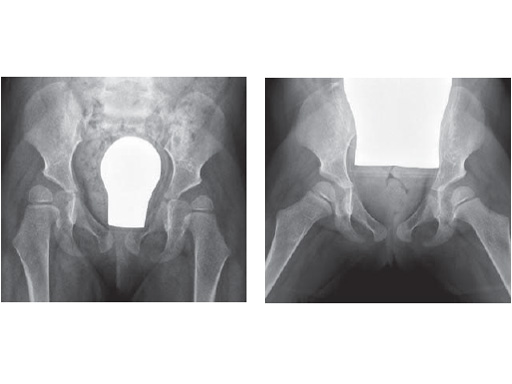

Fig. 1

X-ray after 7 weeks, postoperative treatment with hip spica due to triple OT show good healing

Fig. 2

X-ray after 11 weeks, in turn the child can run well. The triple OT is now planned on the left!